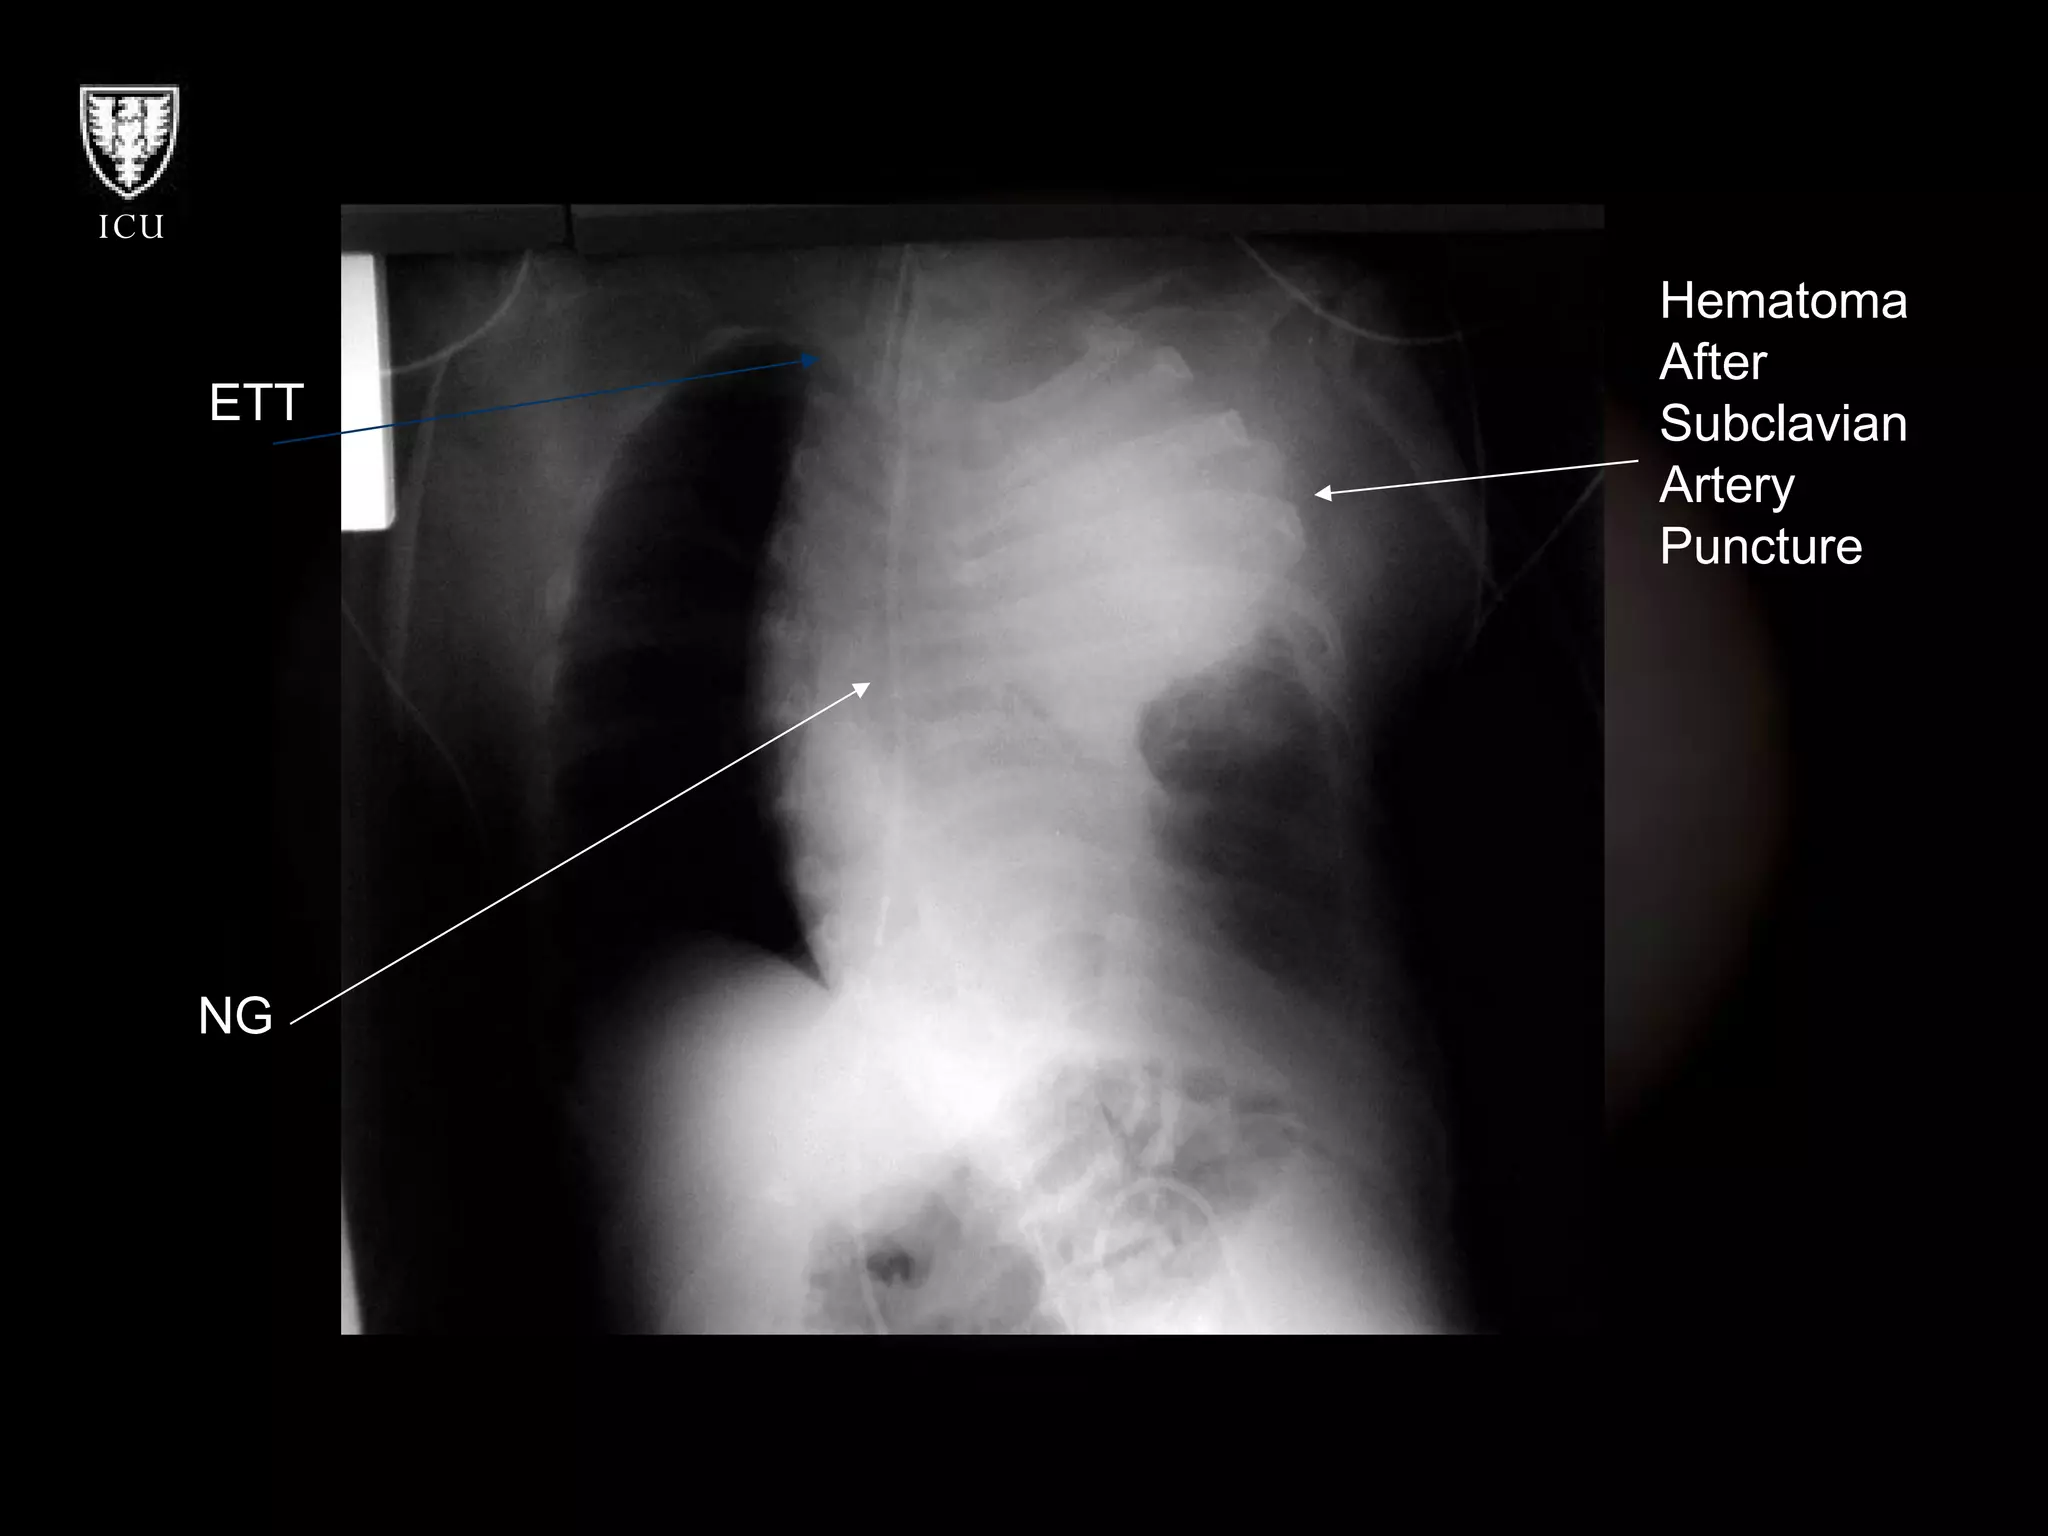

Hematoma After Subclavian Artery Puncture NG ETT

Hematoma After SubclavianArtery Puncture NG ETT